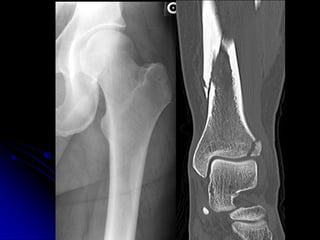

• Review imaging modalities most likely to

definitively diagnose specific acute injuries

(spine, hip)

HIP FRACTURES